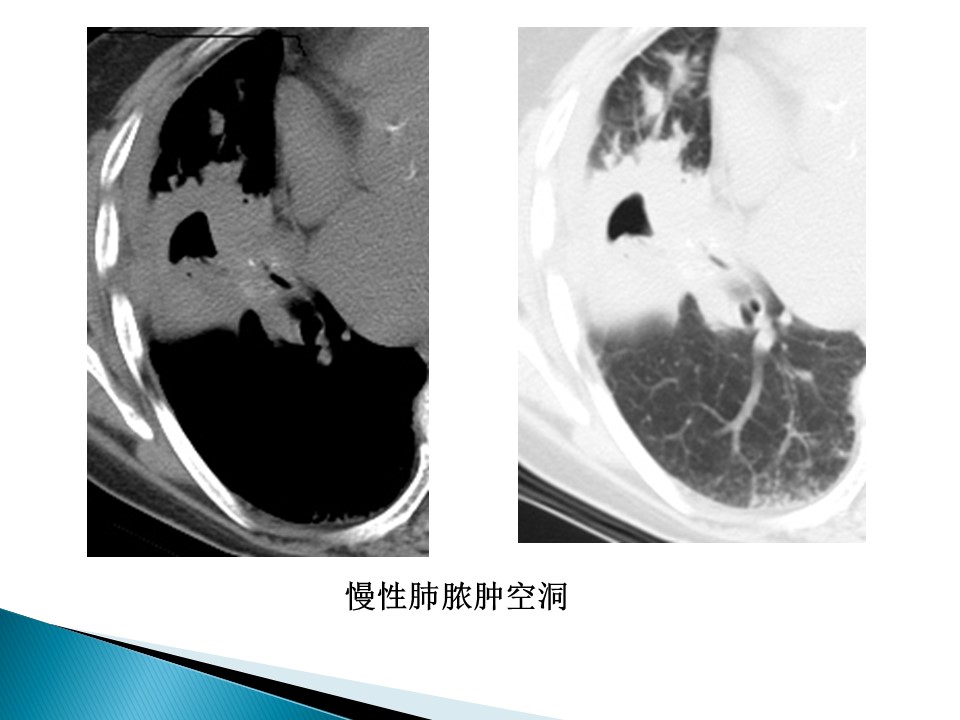

“肺部空洞的CT鉴别诊断PPT” 的相关文章